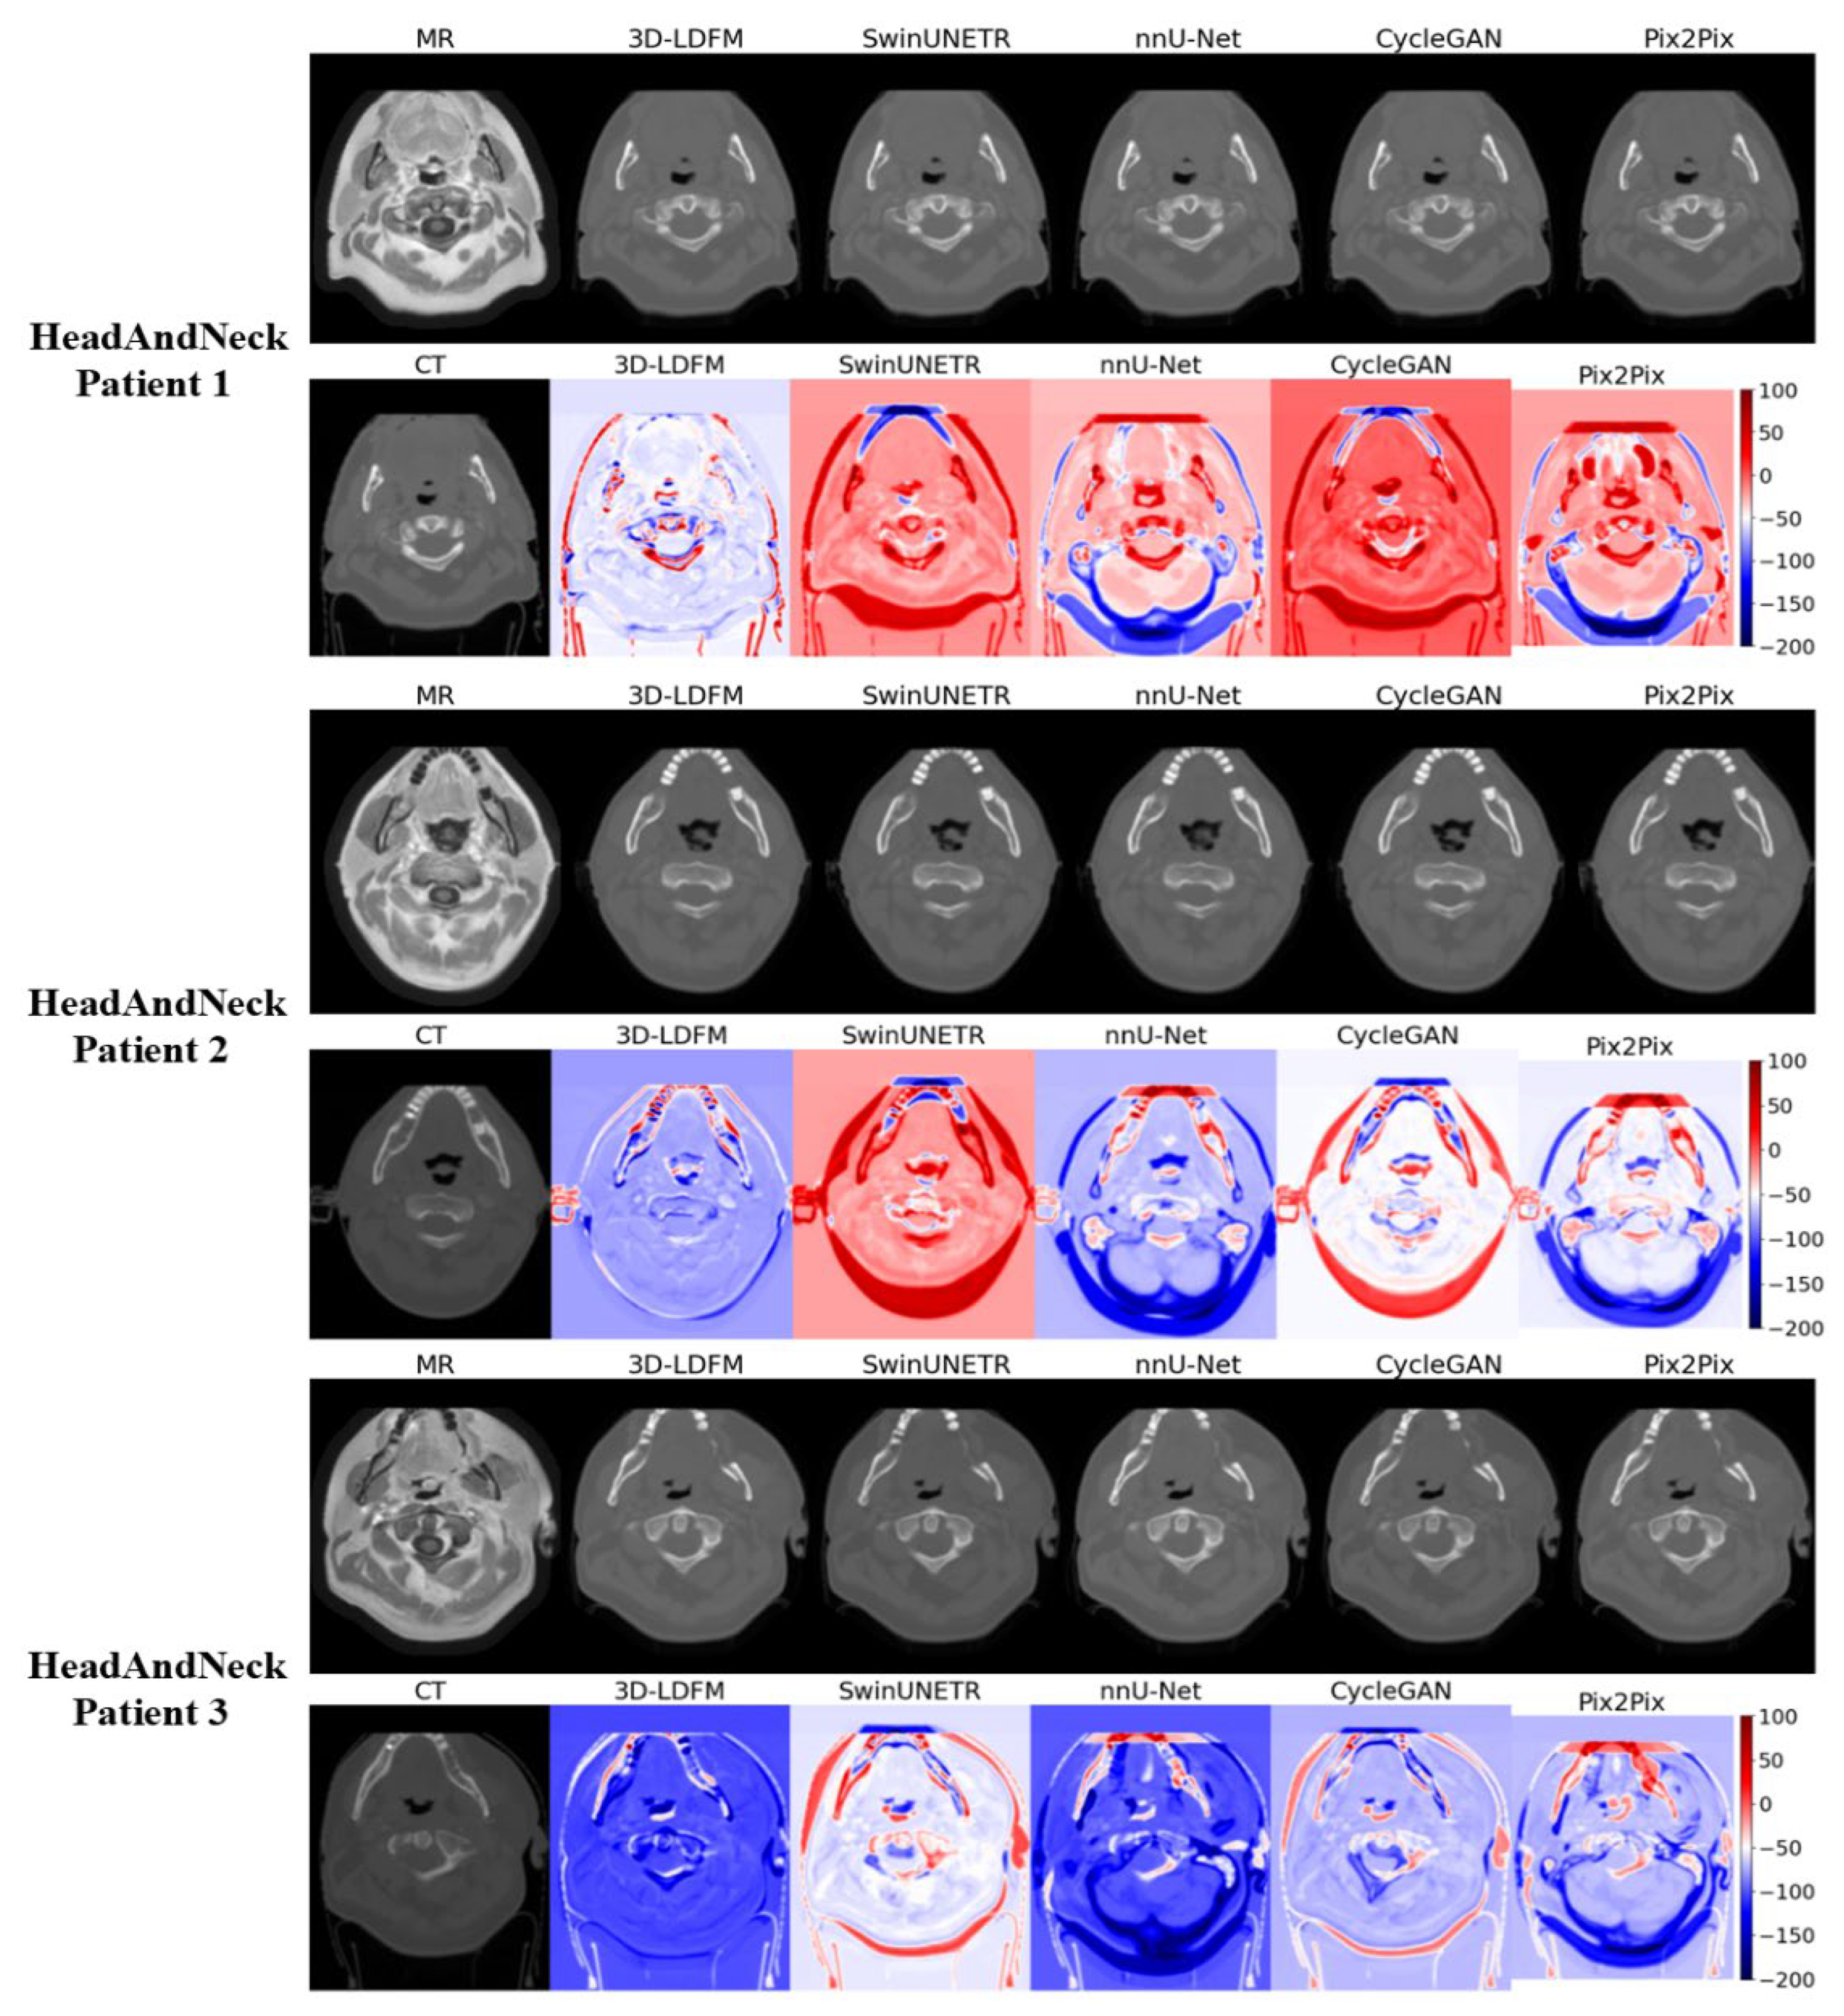

4.2. Assessment and Error Mapping